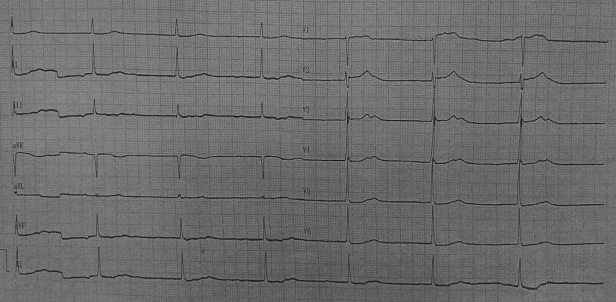

术前心电图

术后即刻心电图